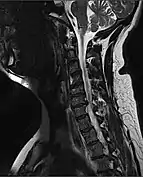

MRI of a fractured and dislocated cervical vertebra (C4) in the neck that is compressing the spinal cord

A radiographic evaluation using an X-ray, CT scan, or MRI can determine if there is damage to the spinal column and where it is located.[9] X-rays are commonly available[88] and can detect instability or misalignment of the spinal column, but do not give very detailed images and can miss injuries to the spinal cord or displacement of ligaments or disks that do not have accompanying spinal column damage.[9] Thus when X-ray findings are normal but SCI is still suspected due to pain or SCI symptoms, CT or MRI scans are used.[88] CT gives greater detail than X-rays, but exposes the patient to more radiation,[90] and it still does not give images of the spinal cord or ligaments; MRI shows body structures in the greatest detail.[9] Thus it is the standard for anyone who has neurological deficits found in SCI or is thought to have an unstable spinal column injury.[91]